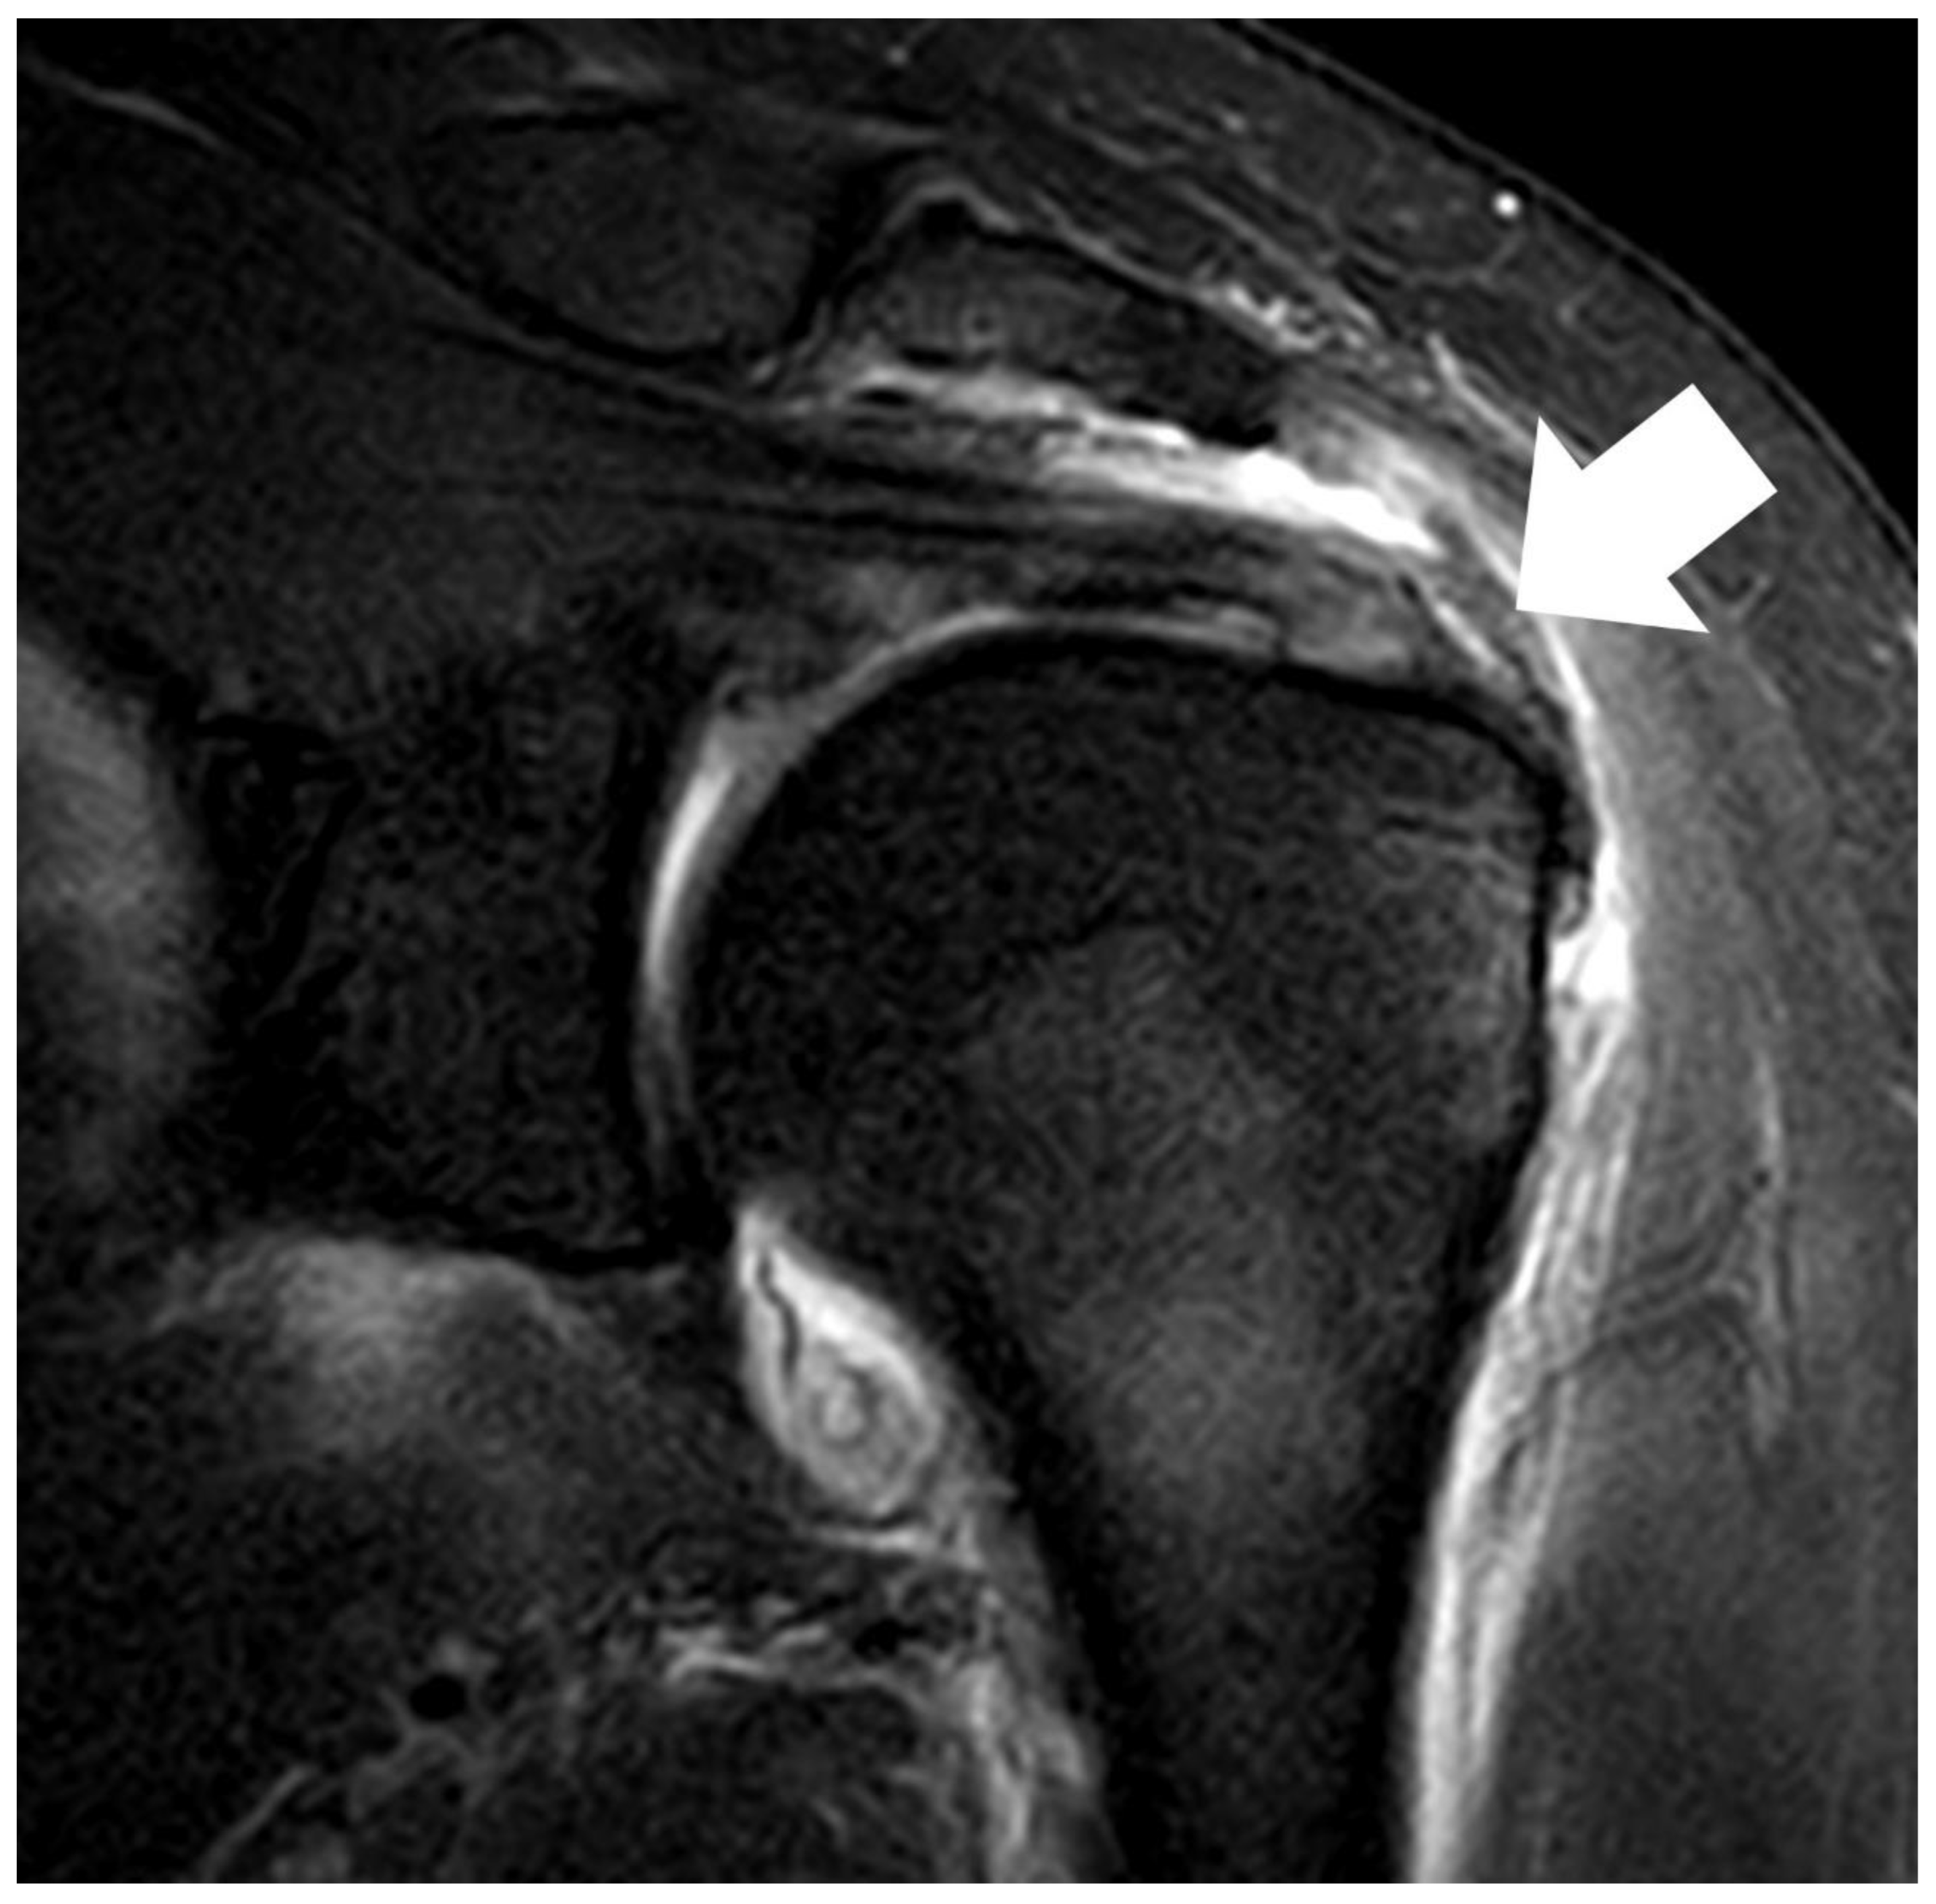

Figure 2. (A) Bursal side partial thickness supraspinatus tear with subacromial spur was observed on the preoperative magnetic resonance imaging. (B) Bio-inductive collagen implant located on the tendon is observed in a post-operative magnetic resonance image. (C) A magnetic resonance image 6 months after surgery showed that the bio-inductive collagen implant was absorbed and the bursal side partial tear was fully recovered.